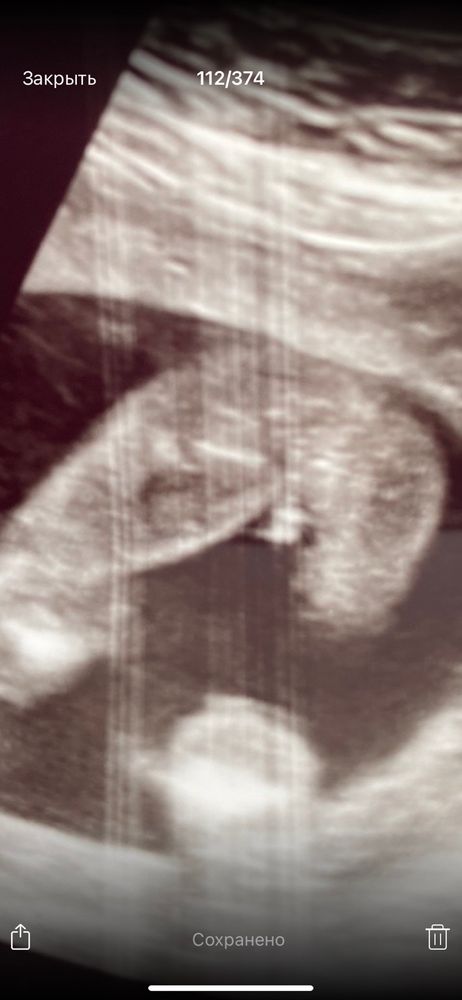

Определение пола по узи

Пол малышаПосле скрининга дали такие фото, но пол не сказали . Теперь думай , гадай 😂

Очень близко как-то расположено к попе))) Похоже на девочку. Но ещё может подрасти))))

Ответ на этот вопрос очень зависит от срока ))

Но мне кажется, это девочка (клитор ещё не закрыт половыми губами)

У мальчиков гораздо больше торчит между ног